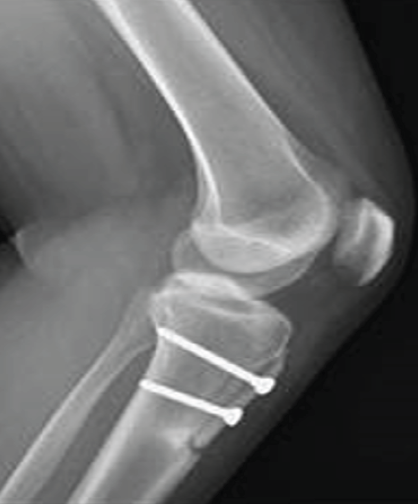

Throughout the 6 weeks, the knee’s range of motion was progressively restored, with flexion not exceeding 90°. Isotonic knee-locking exercises were postponed for 6 weeks, while isometric contractions were encouraged. During a 3-month follow-up outpatient visit, X-rays confirmed the spontaneous onset of a stress fracture of the proximal tibia below the TTO site, showing signs of progression on the next follow-up (Fig. 2). The patient was advised to limit sports activities and postpone dancing. However, the 10-month follow-up evaluation revealed a significant progression of the fracture line, involving two-thirds of the entire tibial diameter, leaving just the posterior cortex intact (Fig. 3).

Figure 2: The lateral view demonstrates signs of a stress fracture along the lower margin of the osteotomy level, observed during the 3-month follow-up evaluation.

Figure 3: Anteroposterior view (a), lateral view (b), and sagittal computed tomography image (c) demonstrate the critical progression of the fracture line, involving two-thirds of the entire tibial diameter.